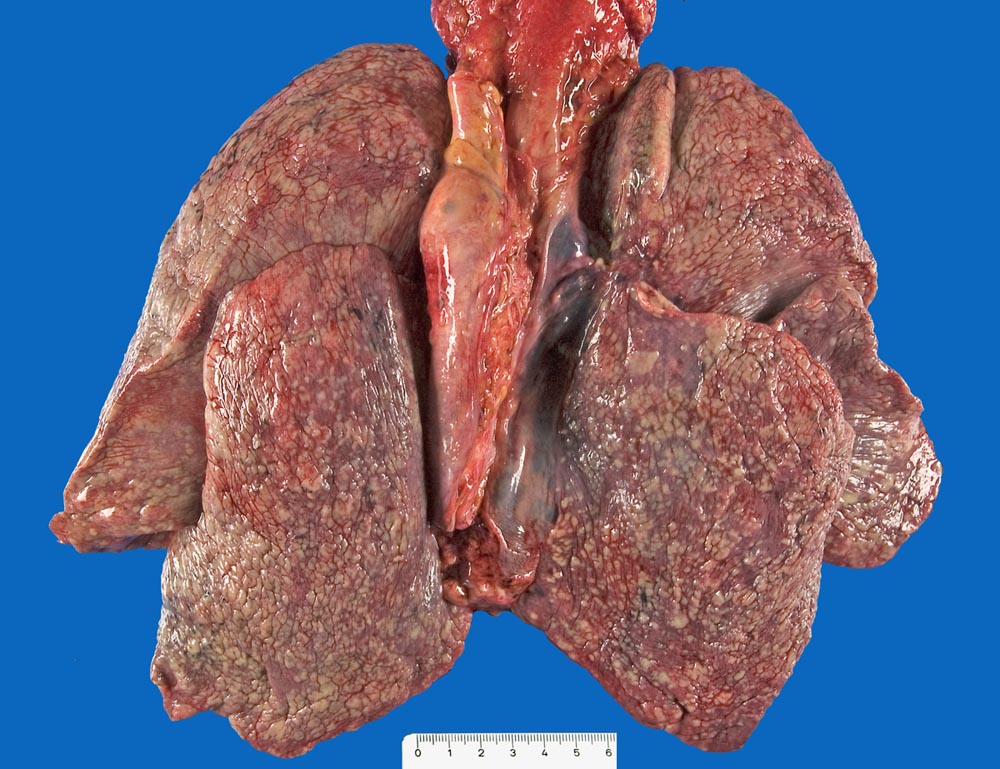

Mammakarzinom: Pleurakarzinose

Diffuse knotige Tumordurchsetzung der Pleura visceralis aller Lungenlappen.

Skelettmetastasen in der Wirbelsäule von zervikal bis sakral sowie des Sternums mit Verdrängung der Hämatopoese. Minimale Restanteile des hämatopoetisch aktiven Knochenmarks (Thrombopenie laut klinischen Angaben). Metastasenleber mit sekundären ischämischen Infarkten. Hämangiosis carcinomatosa des Myokards. Lymphangiosis carcinomatosa der Lungen, des Myokards und des Perikards. Nervenscheideninfiltration des Tumors in der Pleura. Pleurakarzinose (Pleuraerguss rechts: 750ml).

Mässig differenziertes invasiv duktales Mammakarzinom (pT2 pN1 G2). Ablatio mammae vor 14 Jahren. Brustwandrezidiv und Radiotherapie (50 Gy) vor 6 Jahren.